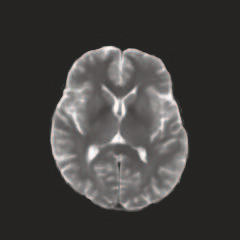

Multi-modal medical image completion has been extensively applied to alleviate the missing modality issue in a wealth of multi-modal diagnostic tasks. However, for most existing synthesis methods, their inferences of missing modalities can collapse into a deterministic mapping from the available ones, ignoring the uncertainties inherent in the cross-modal relationships. Here, we propose the Unified Multi-Modal Conditional Score-based Generative Model (UMM-CSGM) to take advantage of Score-based Generative Model (SGM) in modeling and stochastically sampling a target probability distribution, and further extend SGM to cross-modal conditional synthesis for various missing-modality configurations in a unified framework. Specifically, UMM-CSGM employs a novel multi-in multi-out Conditional Score Network (mm-CSN) to learn a comprehensive set of cross-modal conditional distributions via conditional diffusion and reverse generation in the complete modality space. In this way, the generation process can be accurately conditioned by all available information, and can fit all possible configurations of missing modalities in a single network. Experiments on BraTS19 dataset show that the UMM-CSGM can more reliably synthesize the heterogeneous enhancement and irregular area in tumor-induced lesions for any missing modalities.